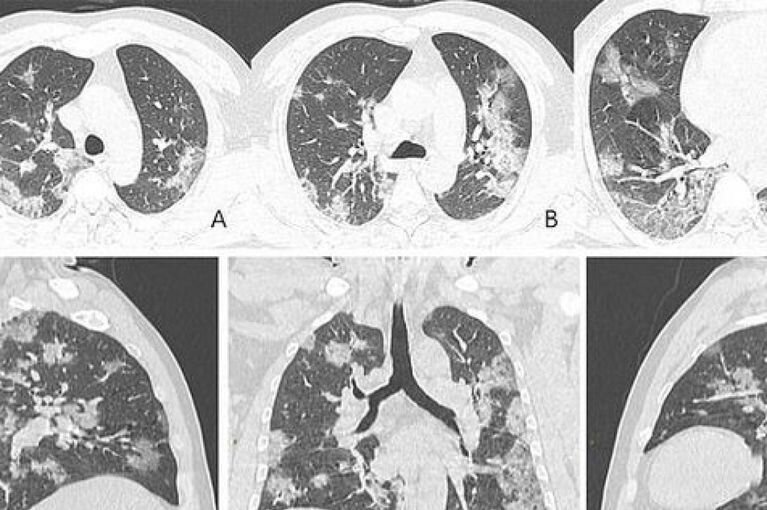

Томография зараженного пациента

Опубликованы рентгеновские снимки и компьютерная томография 44-летнего китайского пациента. По ним хорошо видно, как именно вирус разрушает легочную ткань. По утверждениям медиков, повреждения похожи на те, что обнаруживались в легких жертв атипичной пневмонии и ближневосточного респираторного синдрома.

На фото видны все увеличивающиеся со временем белые пятна в нижней части дыхательных органов. Радиологи называют это симптомом "матового стекла", который отражает различные патологические изменения в легочной ткани.

Отмечается, что на фото заметно присутствие жидкости в легких мужчины, которое постепенно становится все более выраженным (проследить можно по изображению).